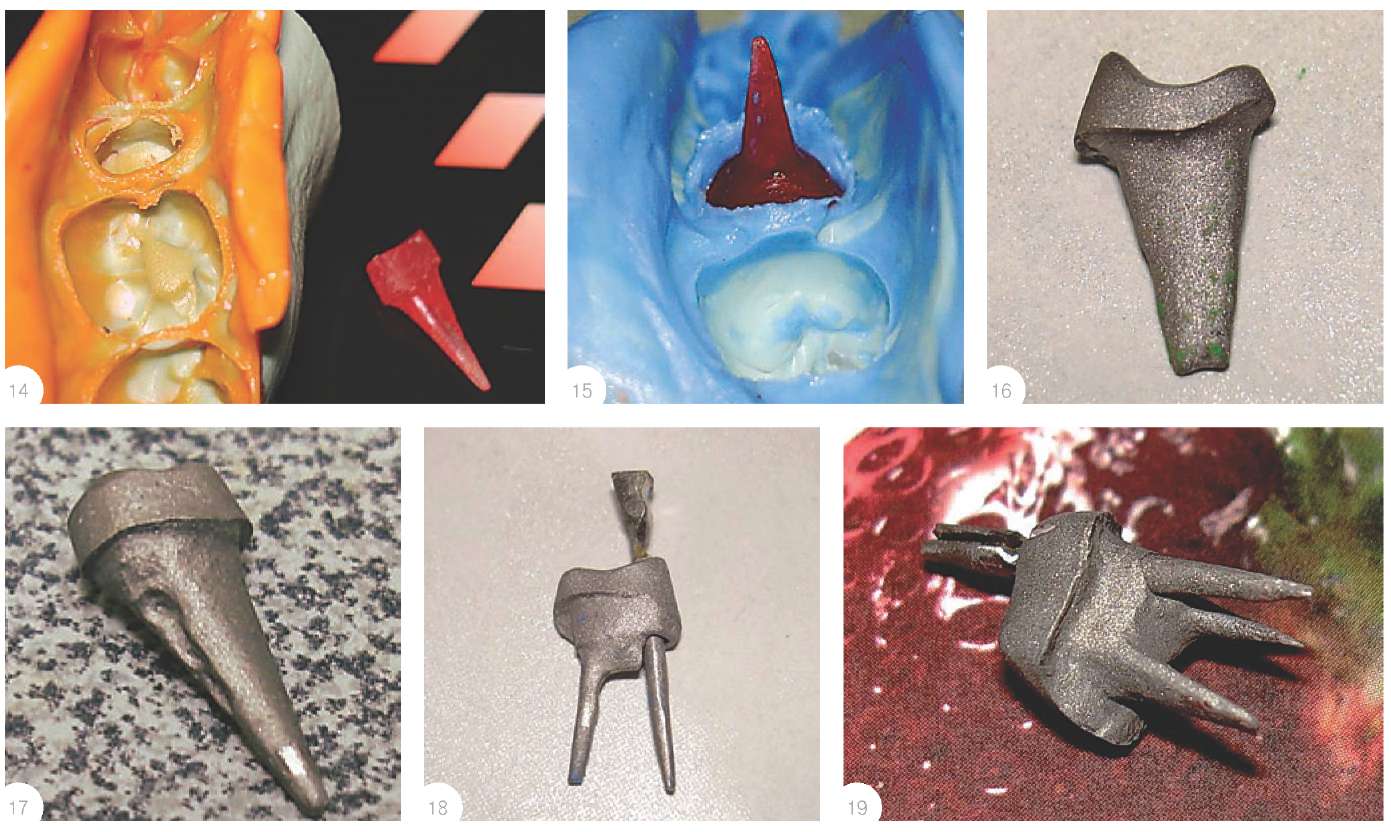

Культя зуба это

Культя зуба это 106 фото